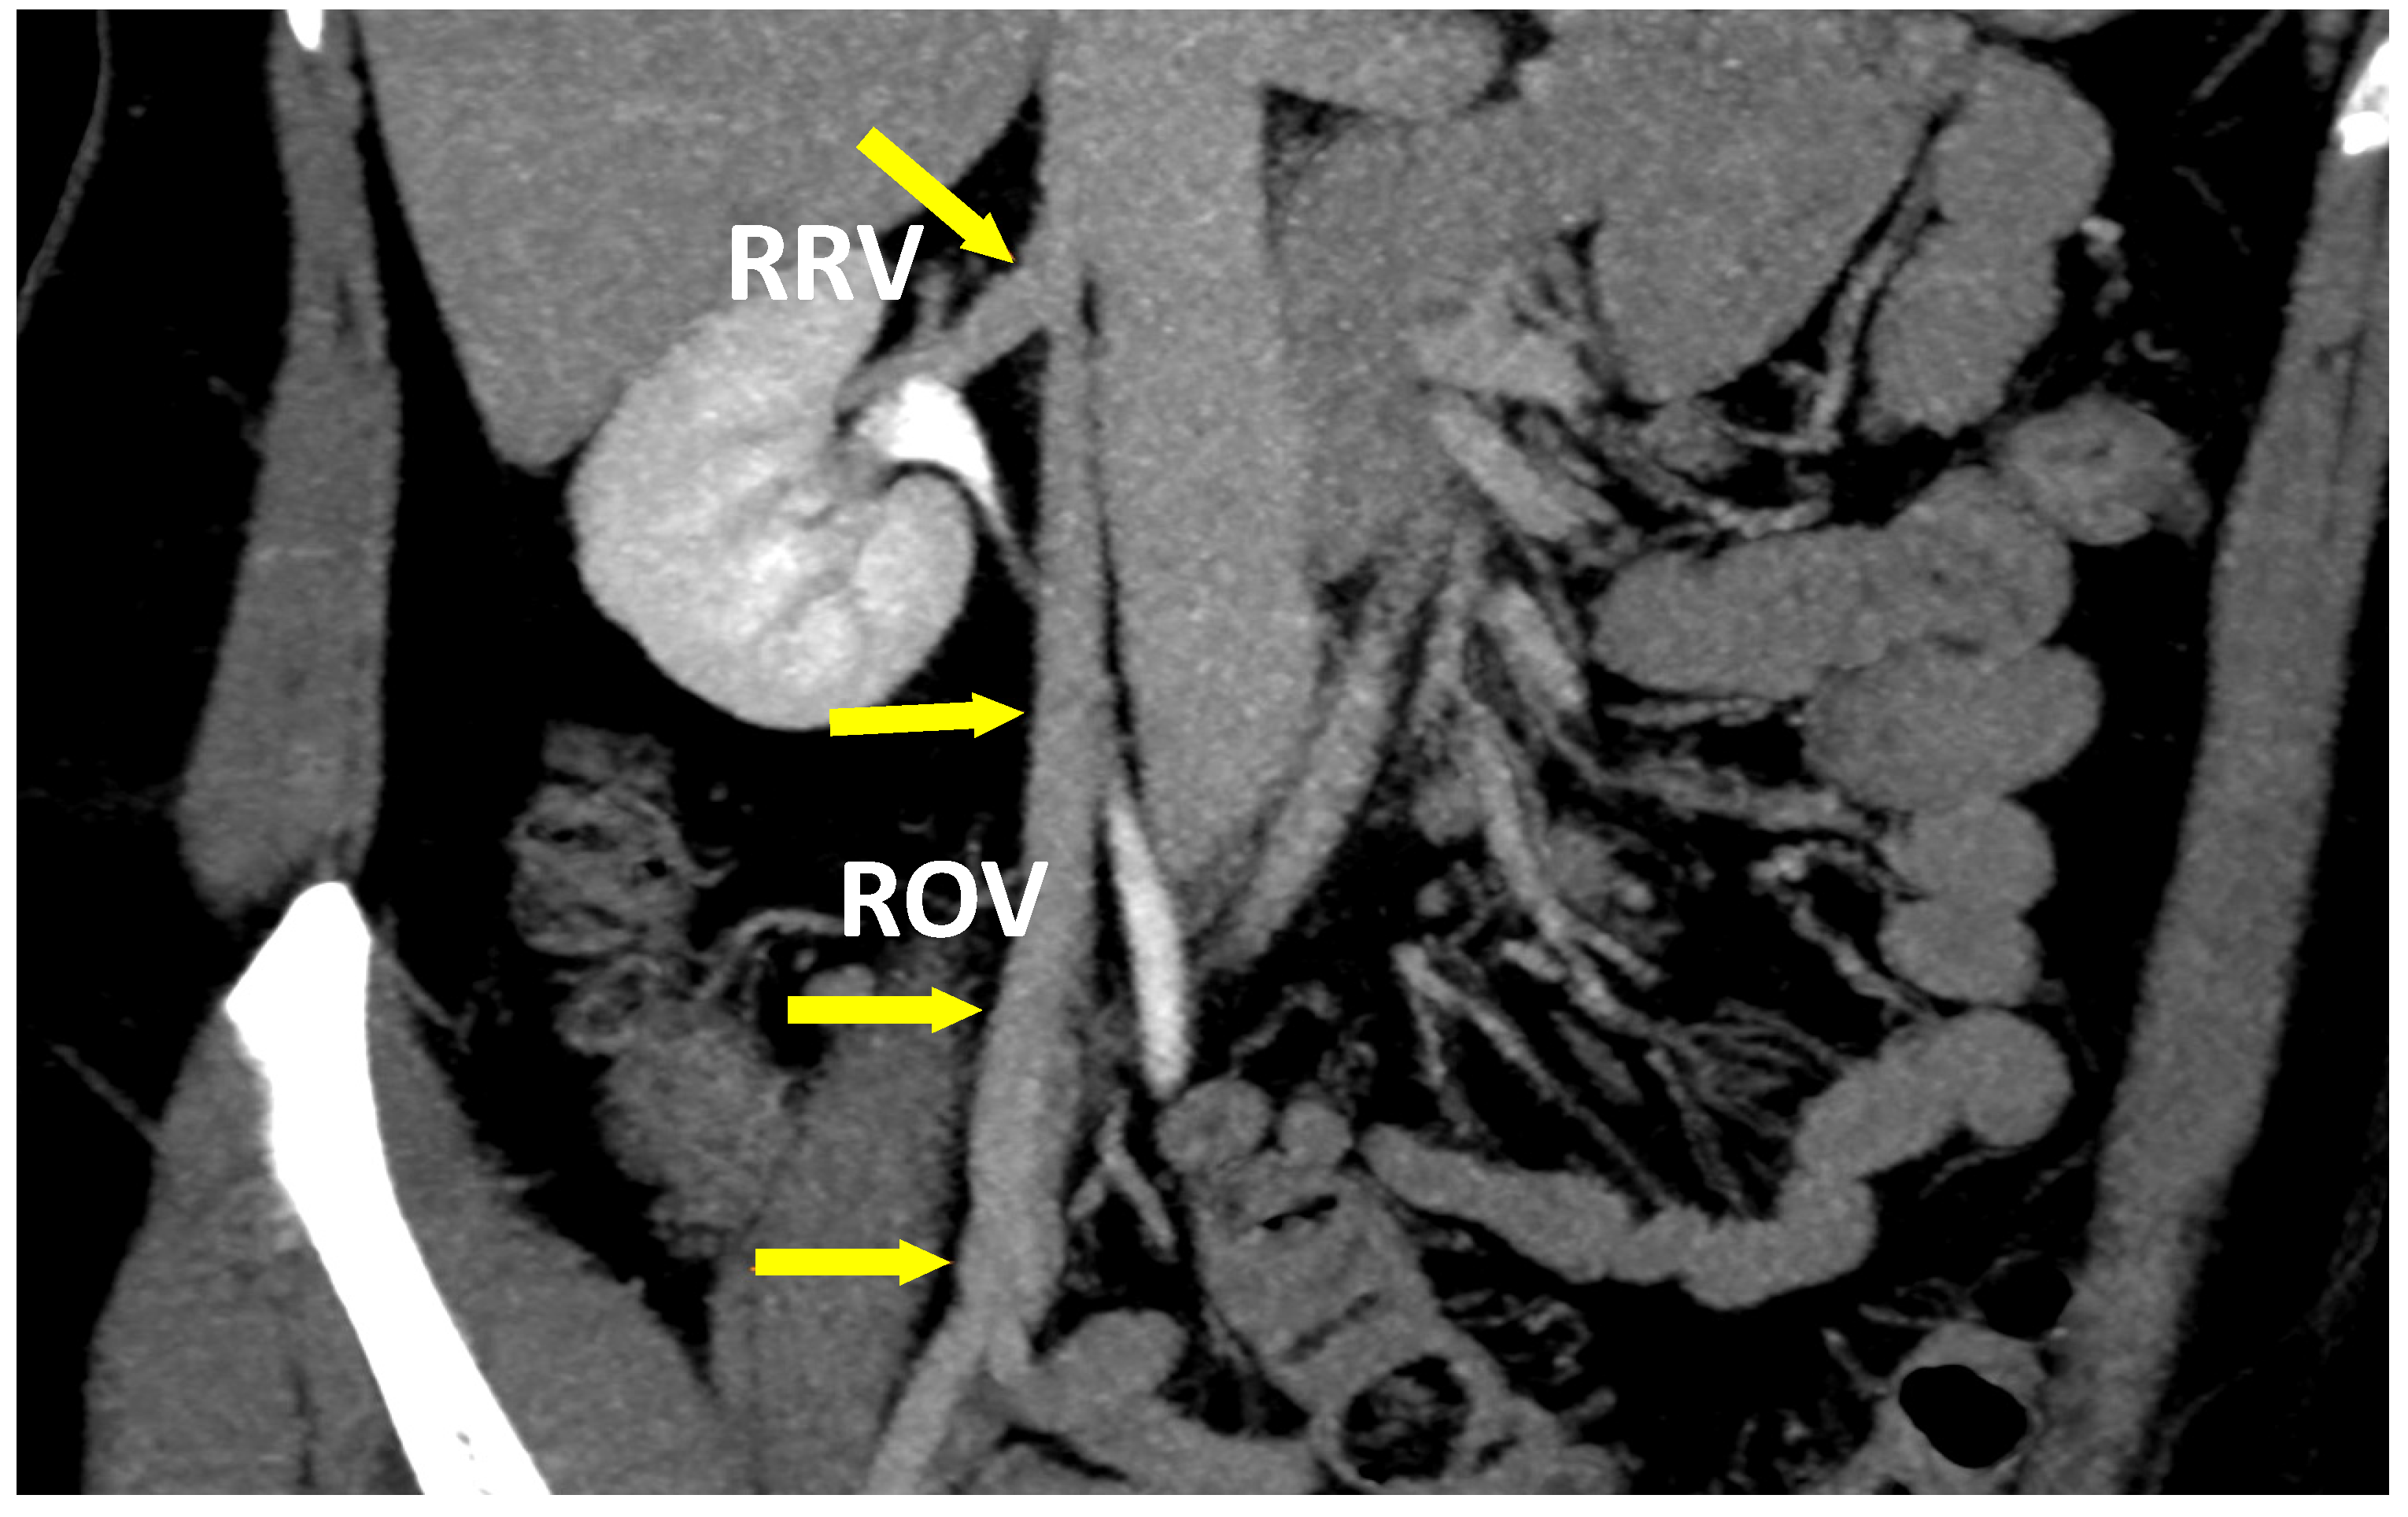

- Szary, C.; Wilczko, J.; Zawadzki, M.; Grzela, T. Hemodynamic and radiological classification of ovarian veins system insufficiency. J. Clin. Med. 2021. under review. [Google Scholar]

| Diameter of LCILV (mm) (1) | 14.1 (14.5) ± 2.2 | 13.4 (13.5) ± 2.7 |

| Diameter of LRV (mm) (2) | 8.1 (9.0) ± 3.8 | 7.8 (9.0) ± 3.6 |

| Diameter of LOV (mm) (3) | 6.7 (6.5) ± 1.9 | 6.6 (6.5) ± 2.1 |

| Diameter of ROV (mm) (3) | 5.8 (5.5) ± 1.7 | 5.9 (5.5) ± 1.9 |

| Reflux in LOV | 125 (68.3%) | 231 (65.6%) |

| Reflux in ROV | 49 (26.8%) | 112 (31.8%) |